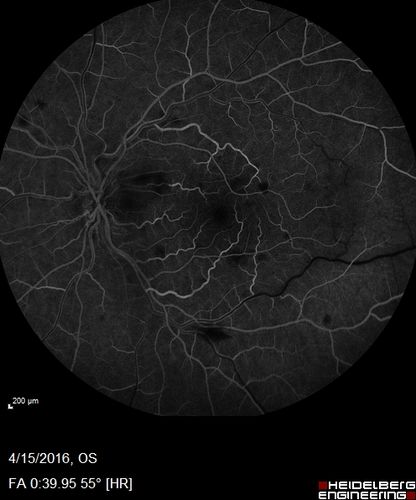

Central retinal artery and vein occlusion - Protein C Deficiency 33 year old male

33 year old male with vision loss for 3 hours.  VA 20/12 right eye, 5/200 left eye.  He has a protein C deficiency.  The left eye recovered vision in about 1 month to 20/16.  FA shows very slow recirculation time.